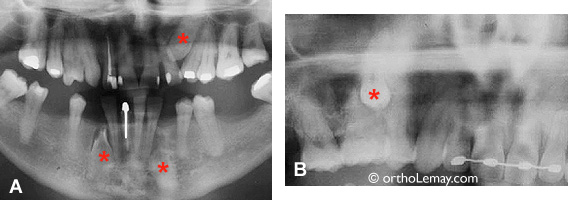

3 canines incluses chez un homme dans la cinquantaine

Exemples de dents incluses et ankylosées qui n’ont pas été extraites même si un traitement d’orthodontie a été entrepris. (A) 3 canines incluses chez un homme dans la cinquantaine. (B) prémolaire incluse chez une jeune adulte.